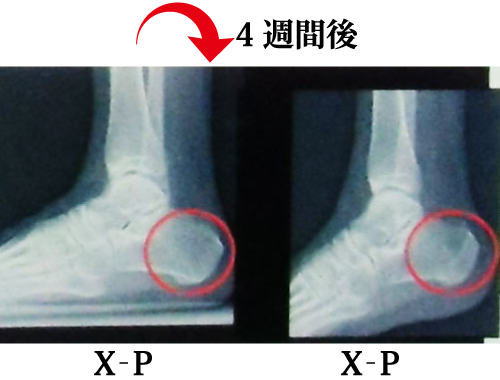

@レントゲン撮影による経過観察

・踵骨骨折